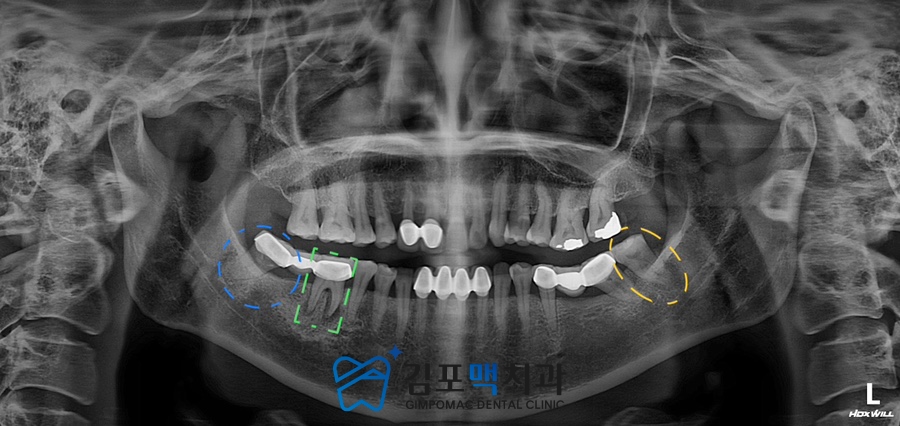

2023.08.03 촬영

치료 전 파노라마 사진입니다.

통증을 호소하신 하악 우측 아래 어금니 부위를

3D-CT를 통해 정밀하게 진.단해 보니

오래전 치료를 받은 브릿지 보철물로 연결된

2개의 치아에 치조골의 일부가 흡수되었고

염증 반응이 확인되었는데요.

교합의 측면에서 봤을 때

정상적인 기능을 할 수 있도록

사랑니는 발치 후 제2대구치(어금니) 자리에

임플란트를 식립하고, 앞쪽 제1대구치는

신경치료와 보철, 교합조정을 통해

자연치를 가능한 살려보는 방향으로

치료 계획을 세웠습니다.

하악 좌측의 대구치(어금니)도

살펴보면 사랑니에 염증이 생겨

음식을 저작할 때마다 불편을 느끼고 있었기에

교합에 문제가 되지 않는다고 판단 후

발치를 진행하기로 결정하였습니다.